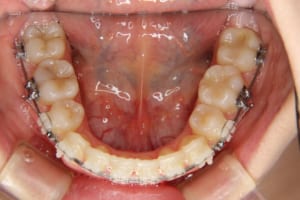

治療中

治療内容 唇側矯正装置を使用した成人矯正治療を行いました。

使用した装置 マルチブラケット装置(唇側矯正)

InVuブラケット

シルバーワイヤー

ホールディングアーチ

歯科矯正用アンカースクリュー(1本)

抜歯および非抜歯 上顎:右側中切歯、右側側切歯、左側第一小臼歯

下顎:両側第一小臼歯